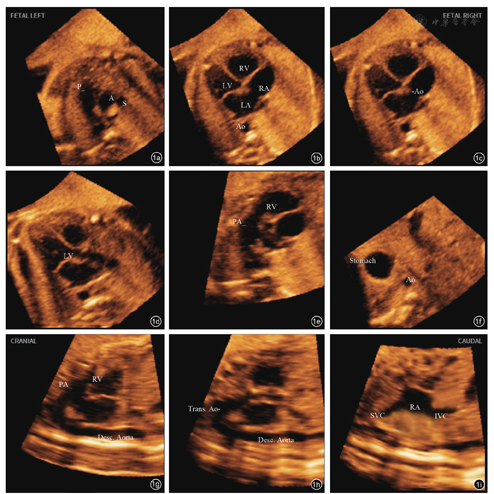

参照国际妇产科超声学会制定的胎儿cTGA超声诊断标准,4个主要诊断切面的诊断要素分别为:3VT(仅见一条大血管,上腔静脉位于右侧);4CV(可以无明显异常,伴或不伴室间隔缺损);LVOT(平行走行的两条大血管,起源于右心室的血管未见分支/起源于左心室的血管可见分支);RVOT(主肺动脉交叉环抱关系消失)。把各诊断要素按图像质量分为3个等级进行评分(图2[16]:结构显示清晰3分(优);结构可以辨认,但不够清晰2分(一般);结构不能辨认1分(差)。2名经验相对不足的医师(医师A和医师B)对每个胎儿容积数据应用5D-Heart软件联合内置的VIS-Assistance®优化处理后进行图像评分,医师A在2周之后再次对图像处理后进行复评。每个诊断切面内各要素所得总分除以要素个数视为该心脏切面的得分,图像获取成功标准为诊断平面内每个要素得分≥2分。

图2 四腔心切面为例进行切面图像质量评分。图a为1分;图b为2分;图c为3分